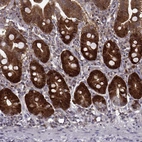

Immunohistochemical staining of human tonsil shows strong cytoplasmic positivity in germinal center cells.